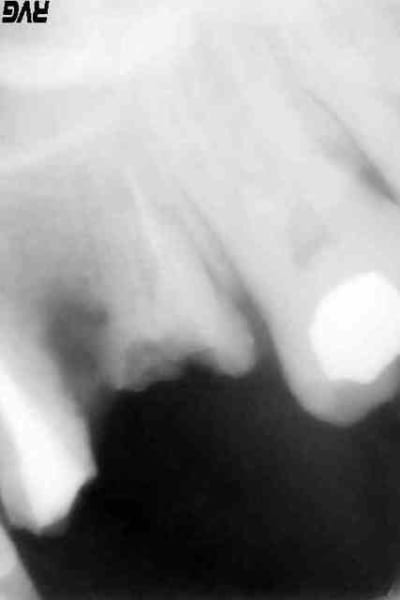

un gars esrt venu suite a un absces carabiné entre 15 ET16.Les dents sont couronnées avec des faux moignons clavettes.le traitement des racines est à l'apex de partout.et pourtant lorsque j'ai incisé l'absces ,il n'y a plus d'os estre la racine mesiale de la 16 et la 15.du vide...que feriez vous? pour moi déposer les couronne et reprndre le ttmt ne servirait a rien. que faire?

comment fait on pout envoyer une radio sur eugenol?elle ne montre rien sinon qu'en mettant une pointe de gutta dans le fistule,on arrive entre 15 ET 16.

J'étais certain que la 26 était causale mais bon, radio sous plusieurs incidences et voilà. (cf radios)